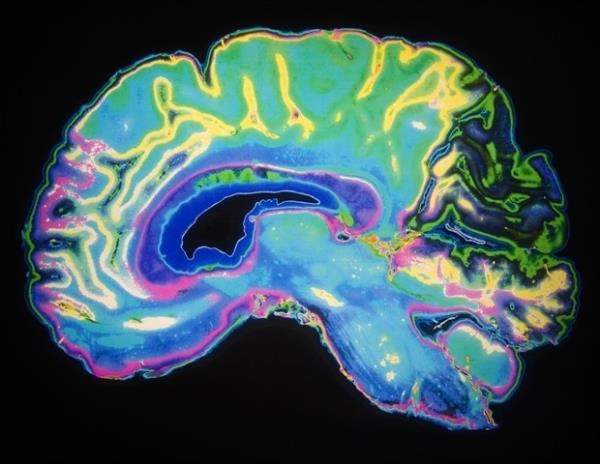

怀孕后大约四到五个月,人类胎儿的前额皮质(PFC)开始出现突触生长的爆发。在这种错综复杂的联系中,发育中的大脑获得了独特的特性,使人类能够进行抽象思维、语言和复杂的社会互动。

人脑发育的标志是在妊娠中期突触突增。这些连接从PFC开始,但随着它们靠近大脑后部的感觉和运动神经元,这些连接逐渐减少。